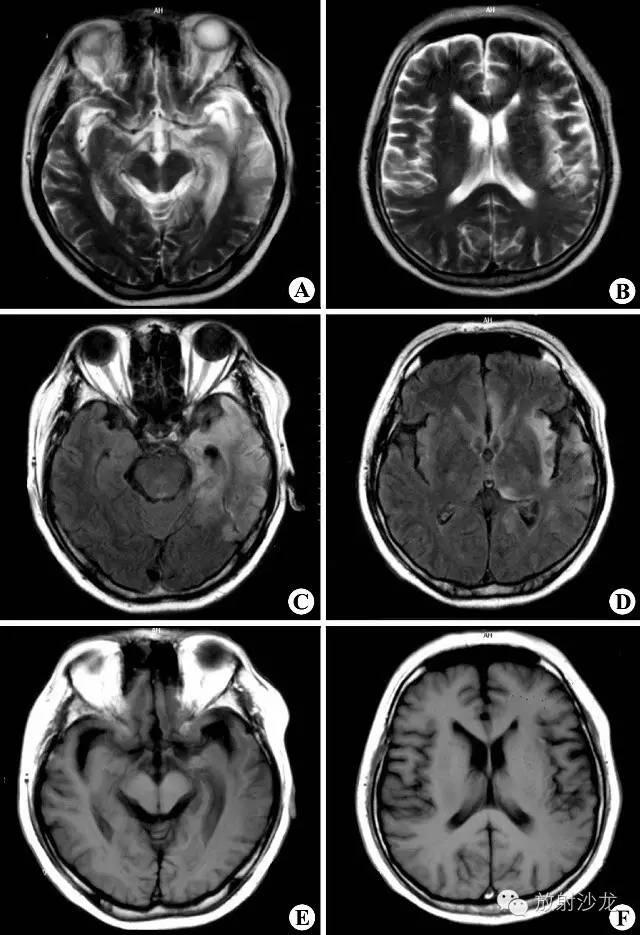

1.2影像学:MRIT1加权像见多发斑点状低信号病灶,通常与侧脑室壁垂直排列,与脑室周围白质内小血管的走行方向一致。陈旧性斑块呈等信号。由于多发硬化是少突神经胶质-血管髓磷脂复合疾病,因此有5%者,皮质和基底节亦受累,半卵圆中心的病灶可有占位效应。脊髓病灶呈长 条形,与脊髓长轴走行一致,一般脊髓不增粗。T2加权像病灶呈高信号,边缘清晰。质子密度加权像有利于显示靠近脑室边缘、脑干及小脑MS病灶。Gd- DTPA增强扫描T1加权像急性脱髓鞘病灶强化,陈旧病灶无强化。 MRI可判断MS的分期:MRI显示病灶大小不变、病灶缩小或数目减少,则提示为缓解期;若病灶增大或数目增多,则提示病情加重。MRI还可用来随访治疗效果。

MRI平扫示双侧侧脑室周围及深部脑白质多发斑片状异常信号区,T1WI(A、B)呈低信号,T2WI(C、D)呈高信号,未见占位效应